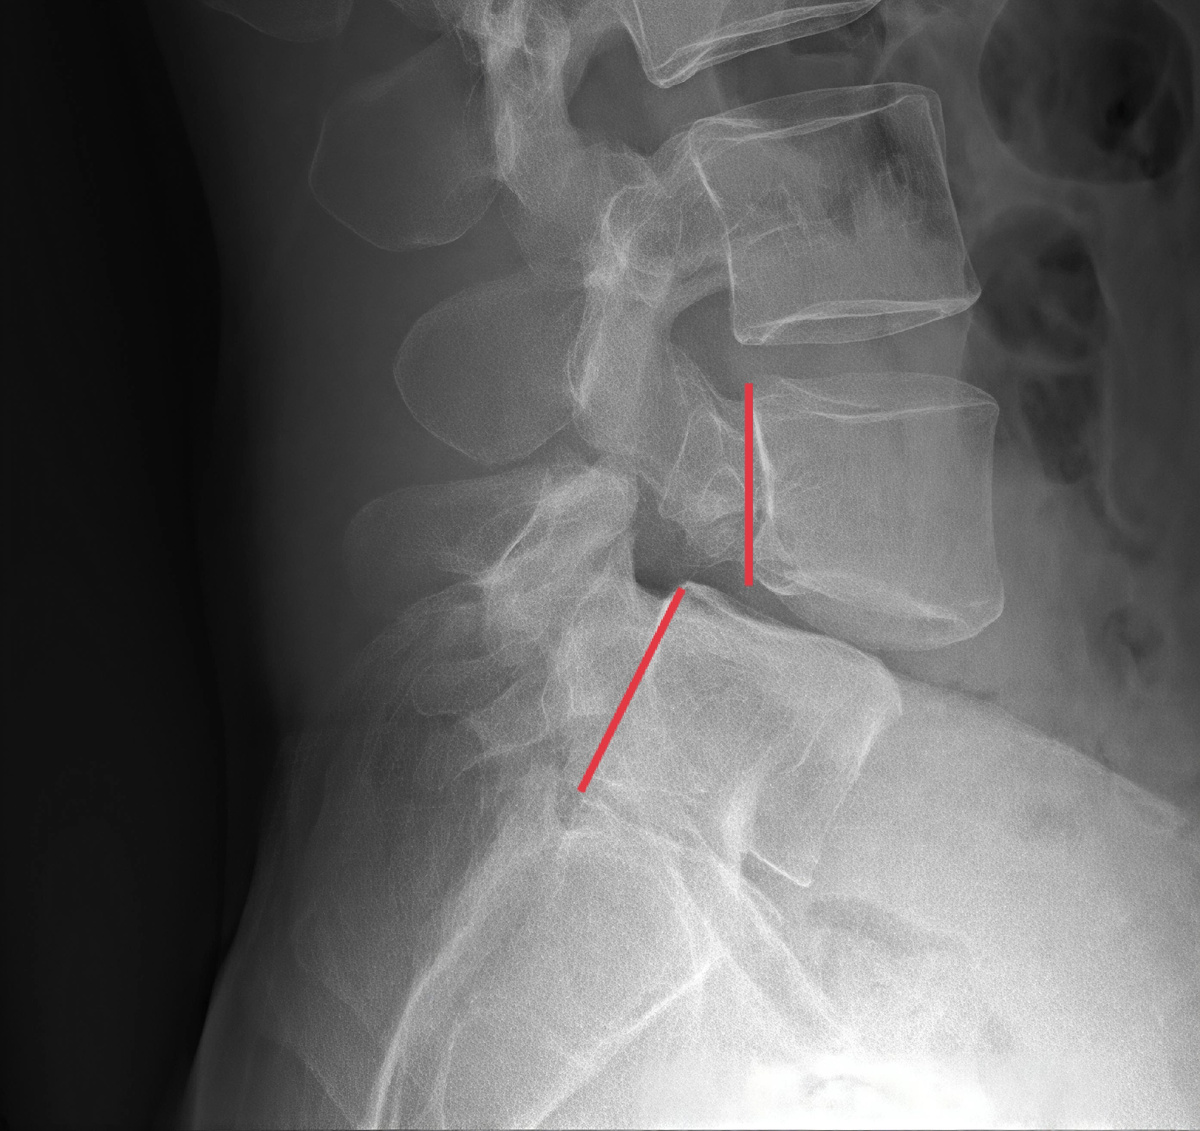

Иллюстрация спондилолистеза

Спондилолистезт на снимке МРТ